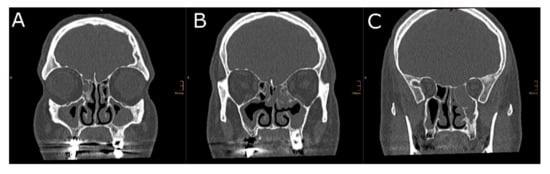

2.3.1. Two-Dimensional Cross-Sectional Analysis